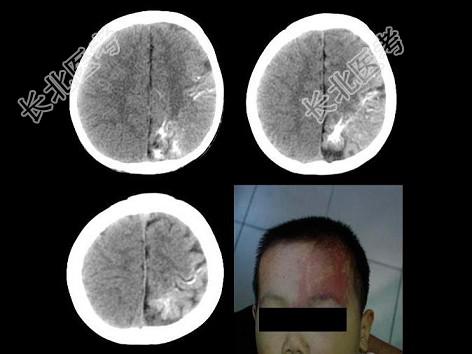

- 单项选择题男,8岁, 出生9个月后常出现发作性癫痫,查体: 右侧肢体轻度萎缩,肌力Ⅳ级, 肌张力增高。结合所示图像,最可能的诊断为 ( )

B、Sturge-Weber综合征